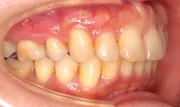

難しいケース2.上顎前突(出っ歯)

上の前歯や上顎が大きく前にでているかみ合わせ。口元が出ていて、出っ歯を治したいという希望の患者さま。23ヶ月という治療期間を経てかみ合わせと口元が改善しました。